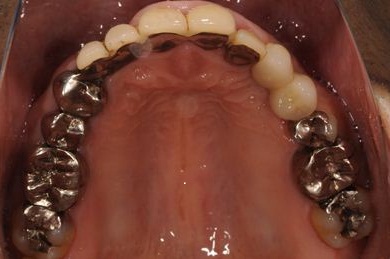

インプラントの症例写真 IMPLANT

抜歯即日スピードインプラント治療

| 治療内容 | インプラント2本(抜歯即日スピードインプラント)、ハイブリッドセラミック2本 | ||||||||||||||||||||||||||||||||